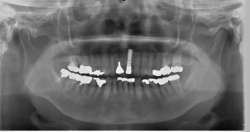

70代男性|前歯の場合

インプラント治療前

インプラント埋入

コンピュータによるシミュレーション